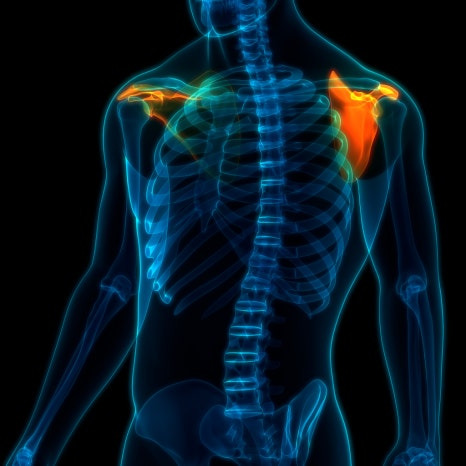

어깨 관절은 우리 몸에서 가장 움직임이 많은 관절입니다. 팔을 앞뒤로 움직이고 위로 들어 올리고 뒤로 돌리는 동작까지 모두 가능하죠. 이렇게 다양한 움직임이 가능한 이유는 회전근개라고 불리는 여러 힘줄이 어깨 관절을 안정적으로 잡아주기 때문입니다. 회전근개는 크게 네 개의 힘줄로 이루어져 있습니다.

이 힘줄들은 팔을 움직일 때 어깨 관절을 중심에 안정적으로 유지하는 역할을 합니다. 그런데 이 부위에 칼슘 성분이 침착되면서 염증이 생기는 질환이 바로 석회성건염입니다. 보통은 한쪽 어깨에서 시작되는 경우가 많지만 생활 습관이나 반복적인 사용 패턴에 따라 양쪽 어깨에서 동시에 나타나는 경우도 있습니다.

석회성건염이란 무엇인가요?

석회성건염은 어깨 힘줄에 석회가 침착되는 질환을 말합니다. 여기서 말하는 석회는 쉽게 말해 칼슘 성분 덩어리인데, 이 물질이 힘줄 내부에 쌓이게 되면 주변 조직에 염증 반응이 나타나면서 통증이 발생할 수 있습니다. 이 질환은 다음과 같은 과정을 거쳐 나타나는 것으로 알려져 있습니다.